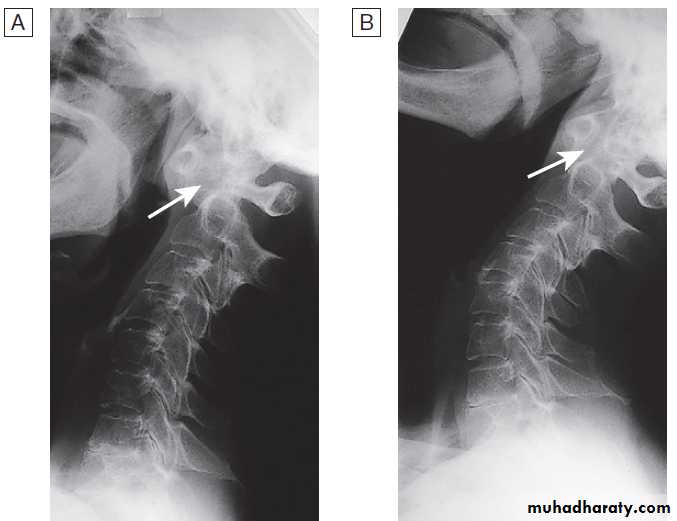

Spine OA

The cervical and lumbar spine are predominantly targeted, then referred to as cervical spondylosis and lumbar spondylosis, respectively . Spine OA may occur in isolation or as part of generalised OA. The typical presentation is with pain localised to the low back region or the neck, although radiation of pain to the arms, buttocks and legs may also occur due to nerve root compression. The pain is typically relieved by restand worse on movement. On physical examination, the

X-ray of spine showing typical changes of

osteoarthritis. Cervical spondylosis showing disc space narrowingbetween C6 and C7, osteophytes at the anterior vertebral body margins (arrows) and osteosclerosis at the apophyseal joints.